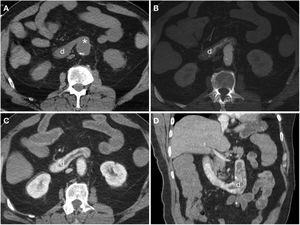

Secondary aortoenteric fistula in a 78-year-old male with a history of aortobifemoral bypass surgery and peptic ulcer disease who sought care due to signs and symptoms of upper gastrointestinal bleeding. Endoscopy revealed an ulceration of the intestinal wall with direct observation of the bypass material. In view of the patient's haemodynamic stability it was decided to assess him by computed tomography. Arterial phase (A), portal phase (B) and MIP reconstruction on the sagittal plane (C). The aortobifemoral bypass was seen to be in intimate contact with the retroperitoneal duodenum presenting a soft-tissue sleeve surrounding the bypass (*) and an ectopic air bubble (arrow tip) with no fat plane for separation. Although active extravasation of IVC was not demonstrated, surgery confirmed the presence of an AEF.

Primary aortoduodenal fistula in a 65-year-old male with an episode of intermittent vomiting and melaena for the past 2 weeks who visited the emergency department with haematemesis, dizziness and hypotension. Baseline computed tomography (A and B) demonstrated high-density (47 HU) content in the gastric chamber in relation to a clot and a calcified aneurysm in the abdominal aorta with an intramural haematoma. The arterial phase (C) revealed a saccular bulge on the anterolateral aspect of the aorta with loss of the fat plane achieving separation with the duodenum (*). The late phase (D) did not demonstrate clear extravasation of IVC. Laparoscopy confirmed the presence of an AEF (E) (a: aorta; d: duodenum; f: fistula) which was repaired in the same surgical procedure (F) including segmental resection of the duodenum.